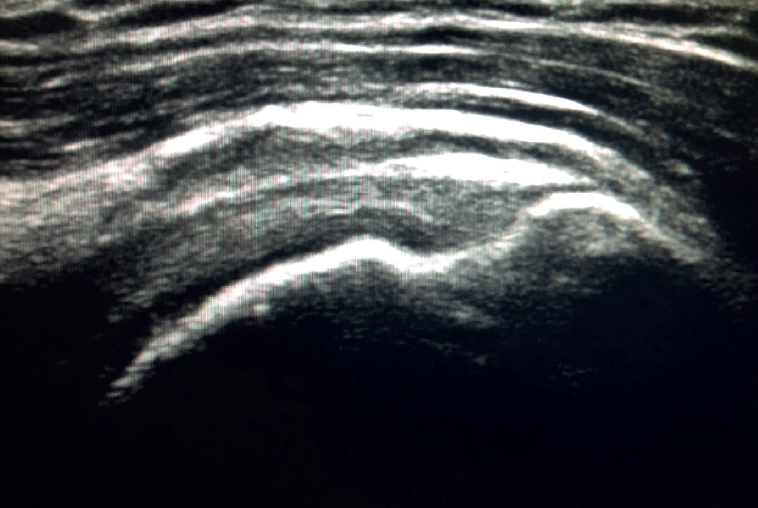

Figure 3. Ultrasound view of severe supraspinatus tendinopathy, with associated bursitis.

The characteristic ultrasound image of tendinosis consists of local or diffuse thickening accompanied by a hypoechogenic and heterogeneous appearance of the tendon (Figure 3). A fine hypoechoic line over 2 mm in thickness between the tendon of the supraspinatus and the subdeltoid adipose tissue corresponds to subacromial-subdeltoid bursitis, and the presence of fluid in the bursa is related to a high probability of partial or complete injury of the tendon of the supraspinatus muscle(26). In order to achieve greater diagnostic accuracy and distinguish between an inflammatory process and a normal small amount of fluid in the bursa, we should take into account that bursitis, tenosynovitis and tendinitis are characterized by the presence of hyperechoic zones with areas of enhanced flow in the Doppler ultrasound study. Both bursal and articular partial ruptures appear as a hypoechoic discontinuity in the tendon that does not vary on modifying the inclination of the ultrasound probe in either the long axis of the tendon nor its short axis(19). This latter aspect is important in order not to confuse partial lesions with anisotropic phenomena, which are a change in tissue behaviour according to the ultrasound angle of incidence(27)(Figure 4).